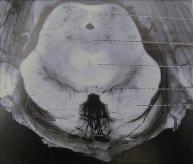

Figure 11 is from a paper by Kant (1933) and shows

petechial (pinpoint-size hemorrhagic spots) in the

inferior colliculi and surrounding areas of the midbrain,

which are characteristic of the damage in Wernicke's

encephalopathy [12]. The early papers, written in

German, describe the damage as small "flea-bite" size

hemorrhages that result from engorgement then

bursting of capillary vessels, similar to the "whiskey

nose" of many alcoholics.

Pinpoint hemorrhages

in the inferior colliculi from

alcohol intoxication

Figure 11 - From Kant (1933). Corpus quadrigeminum posterior, another name for

Pinpoint hemorrhages from chronic alcohol intoxication are evident in the inferior colliculi.